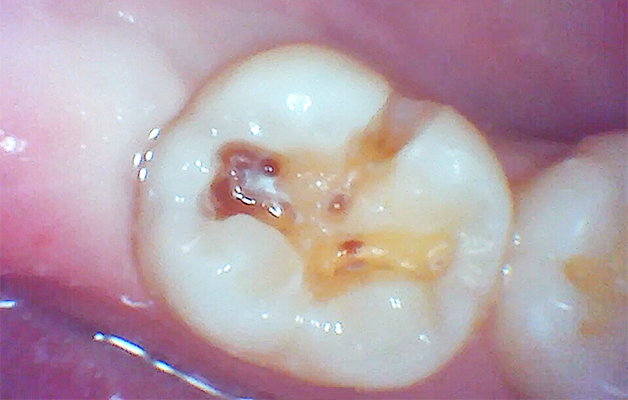

上記は、保険内治療でレジン充填治療(白い詰め物治療)を行った時の写真です。

治療時は口腔内カメラを活用し、治療前、治療中、治療後の状態を出来るだけ分かりやすくお伝えしています。